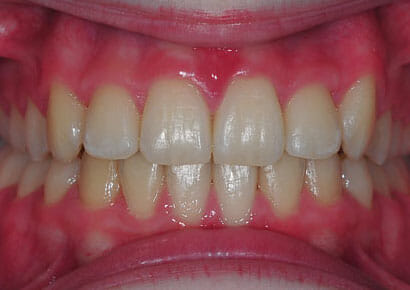

This lady hated her very uneven smile, all the teeth sticking out at the sides, teeth bunched together and uneven. We fitted clear brackets and a wire on the inside in the upper jaw in the roof of the mouth and in under 18 months the teeth were perfectly aligned and the patient’s smile was changed forever.